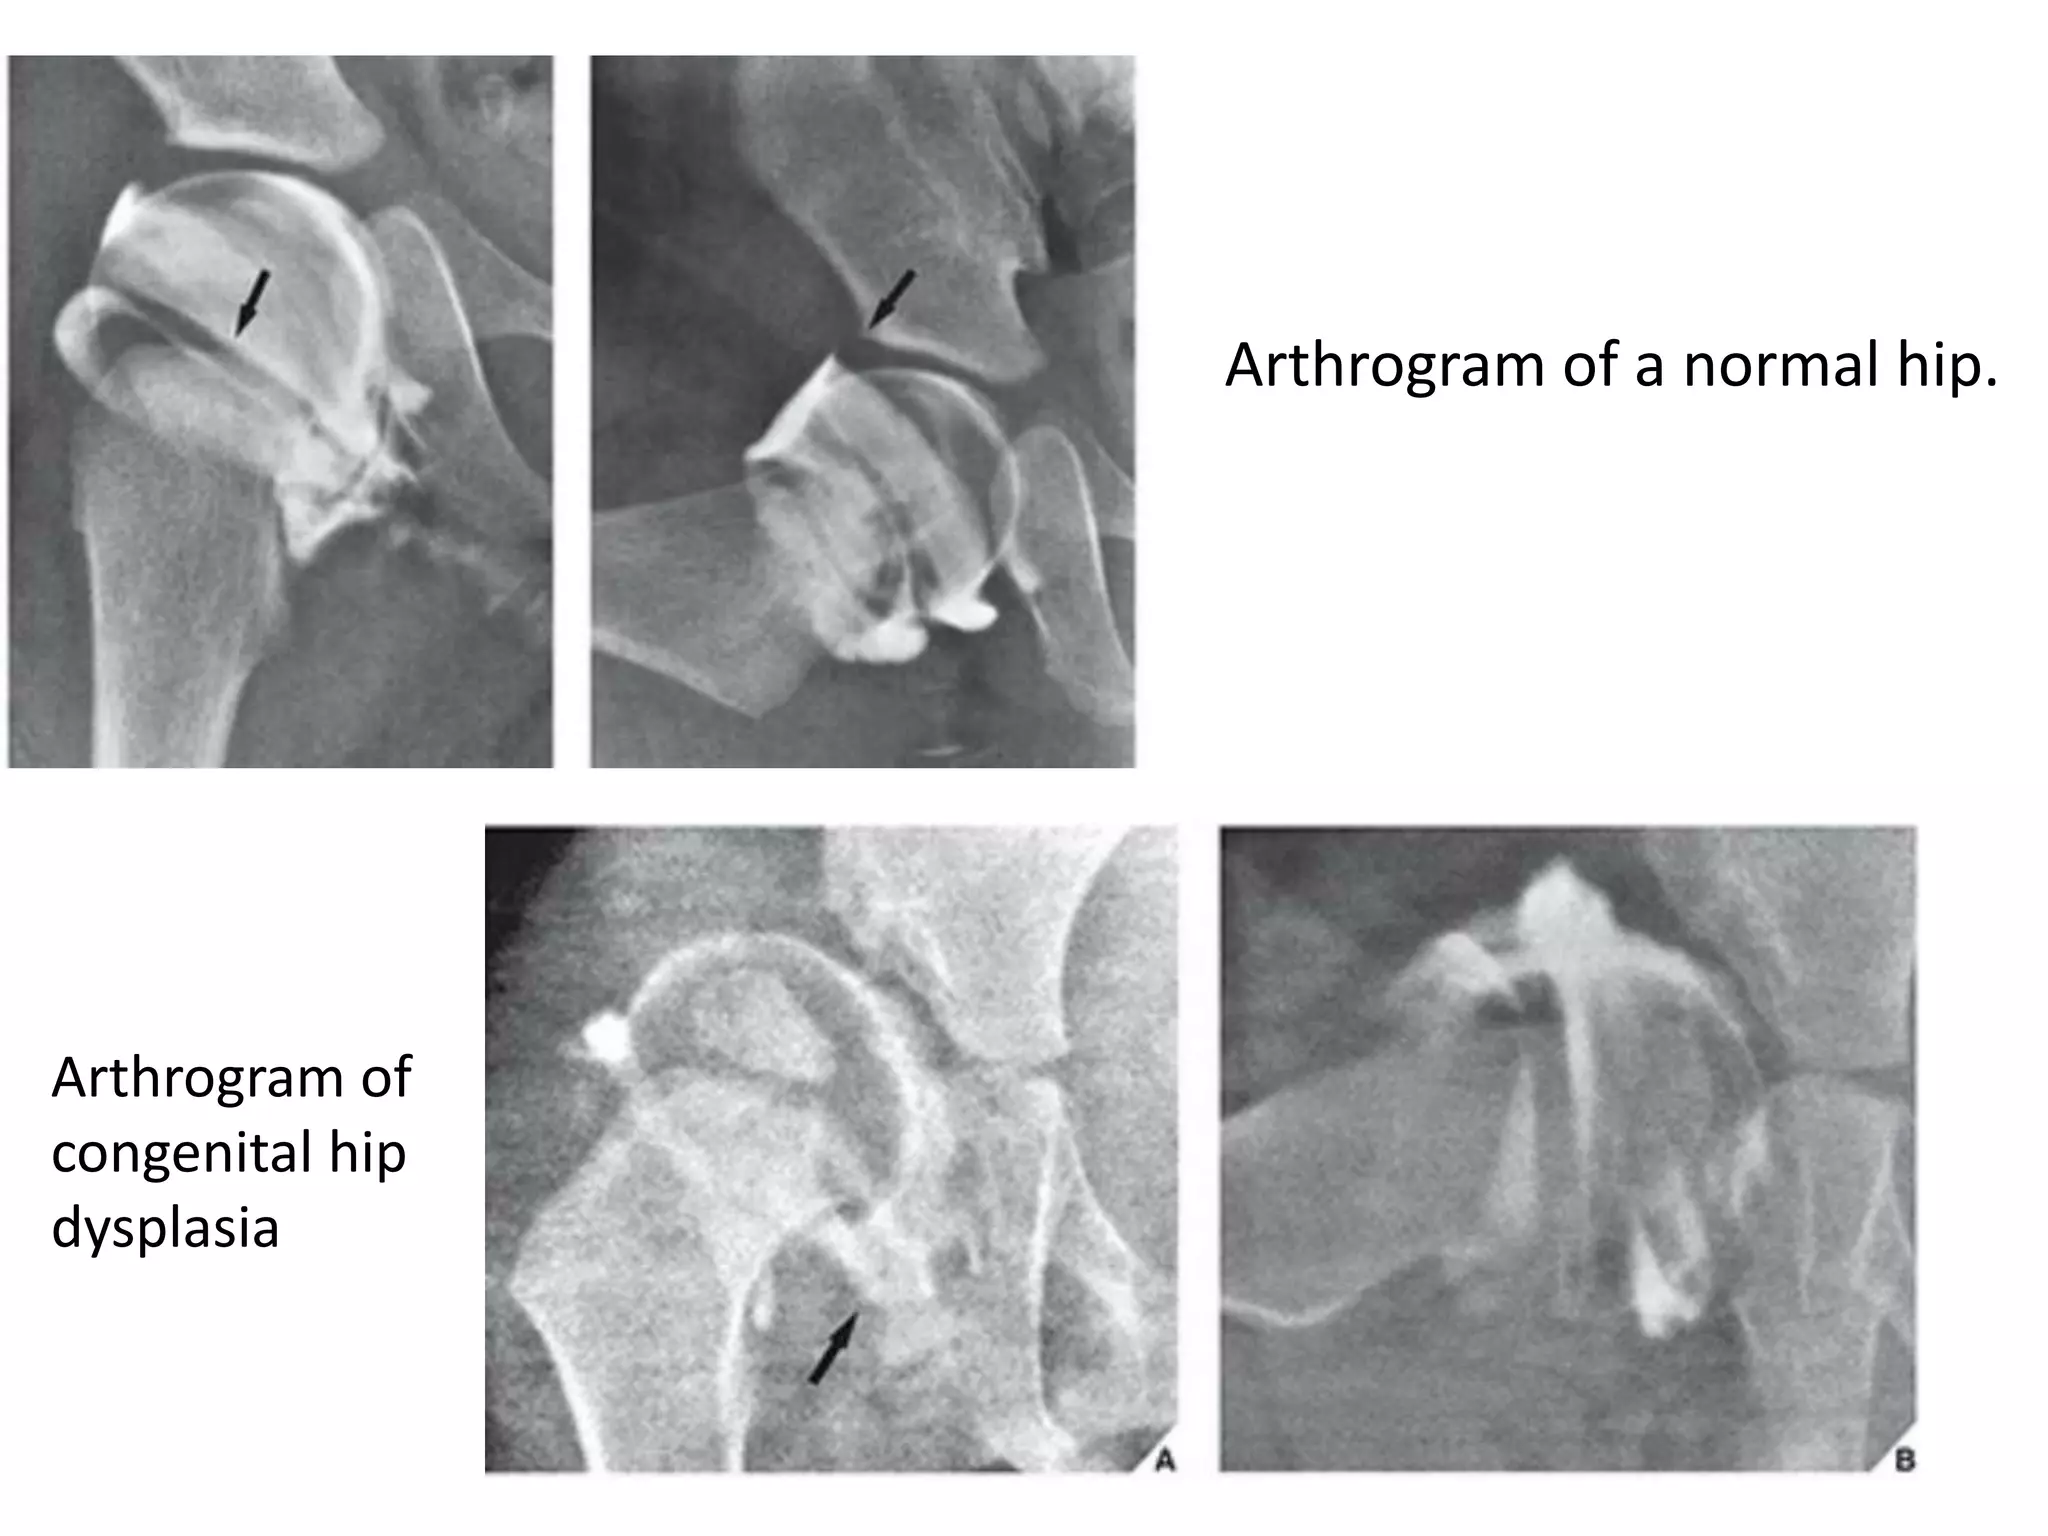

The arthrographic anatomy of the hip was well described by Severin in

1941. In the normal hip, the free border of the labrum is easily seen as a

sharp “thorn” overlying the femoral head.A recess of joint capsule

Arthrogram of a normal hip.

Arthrogram of

congenital hip

dysplasia

Arthrogram of congenital hip dislocation